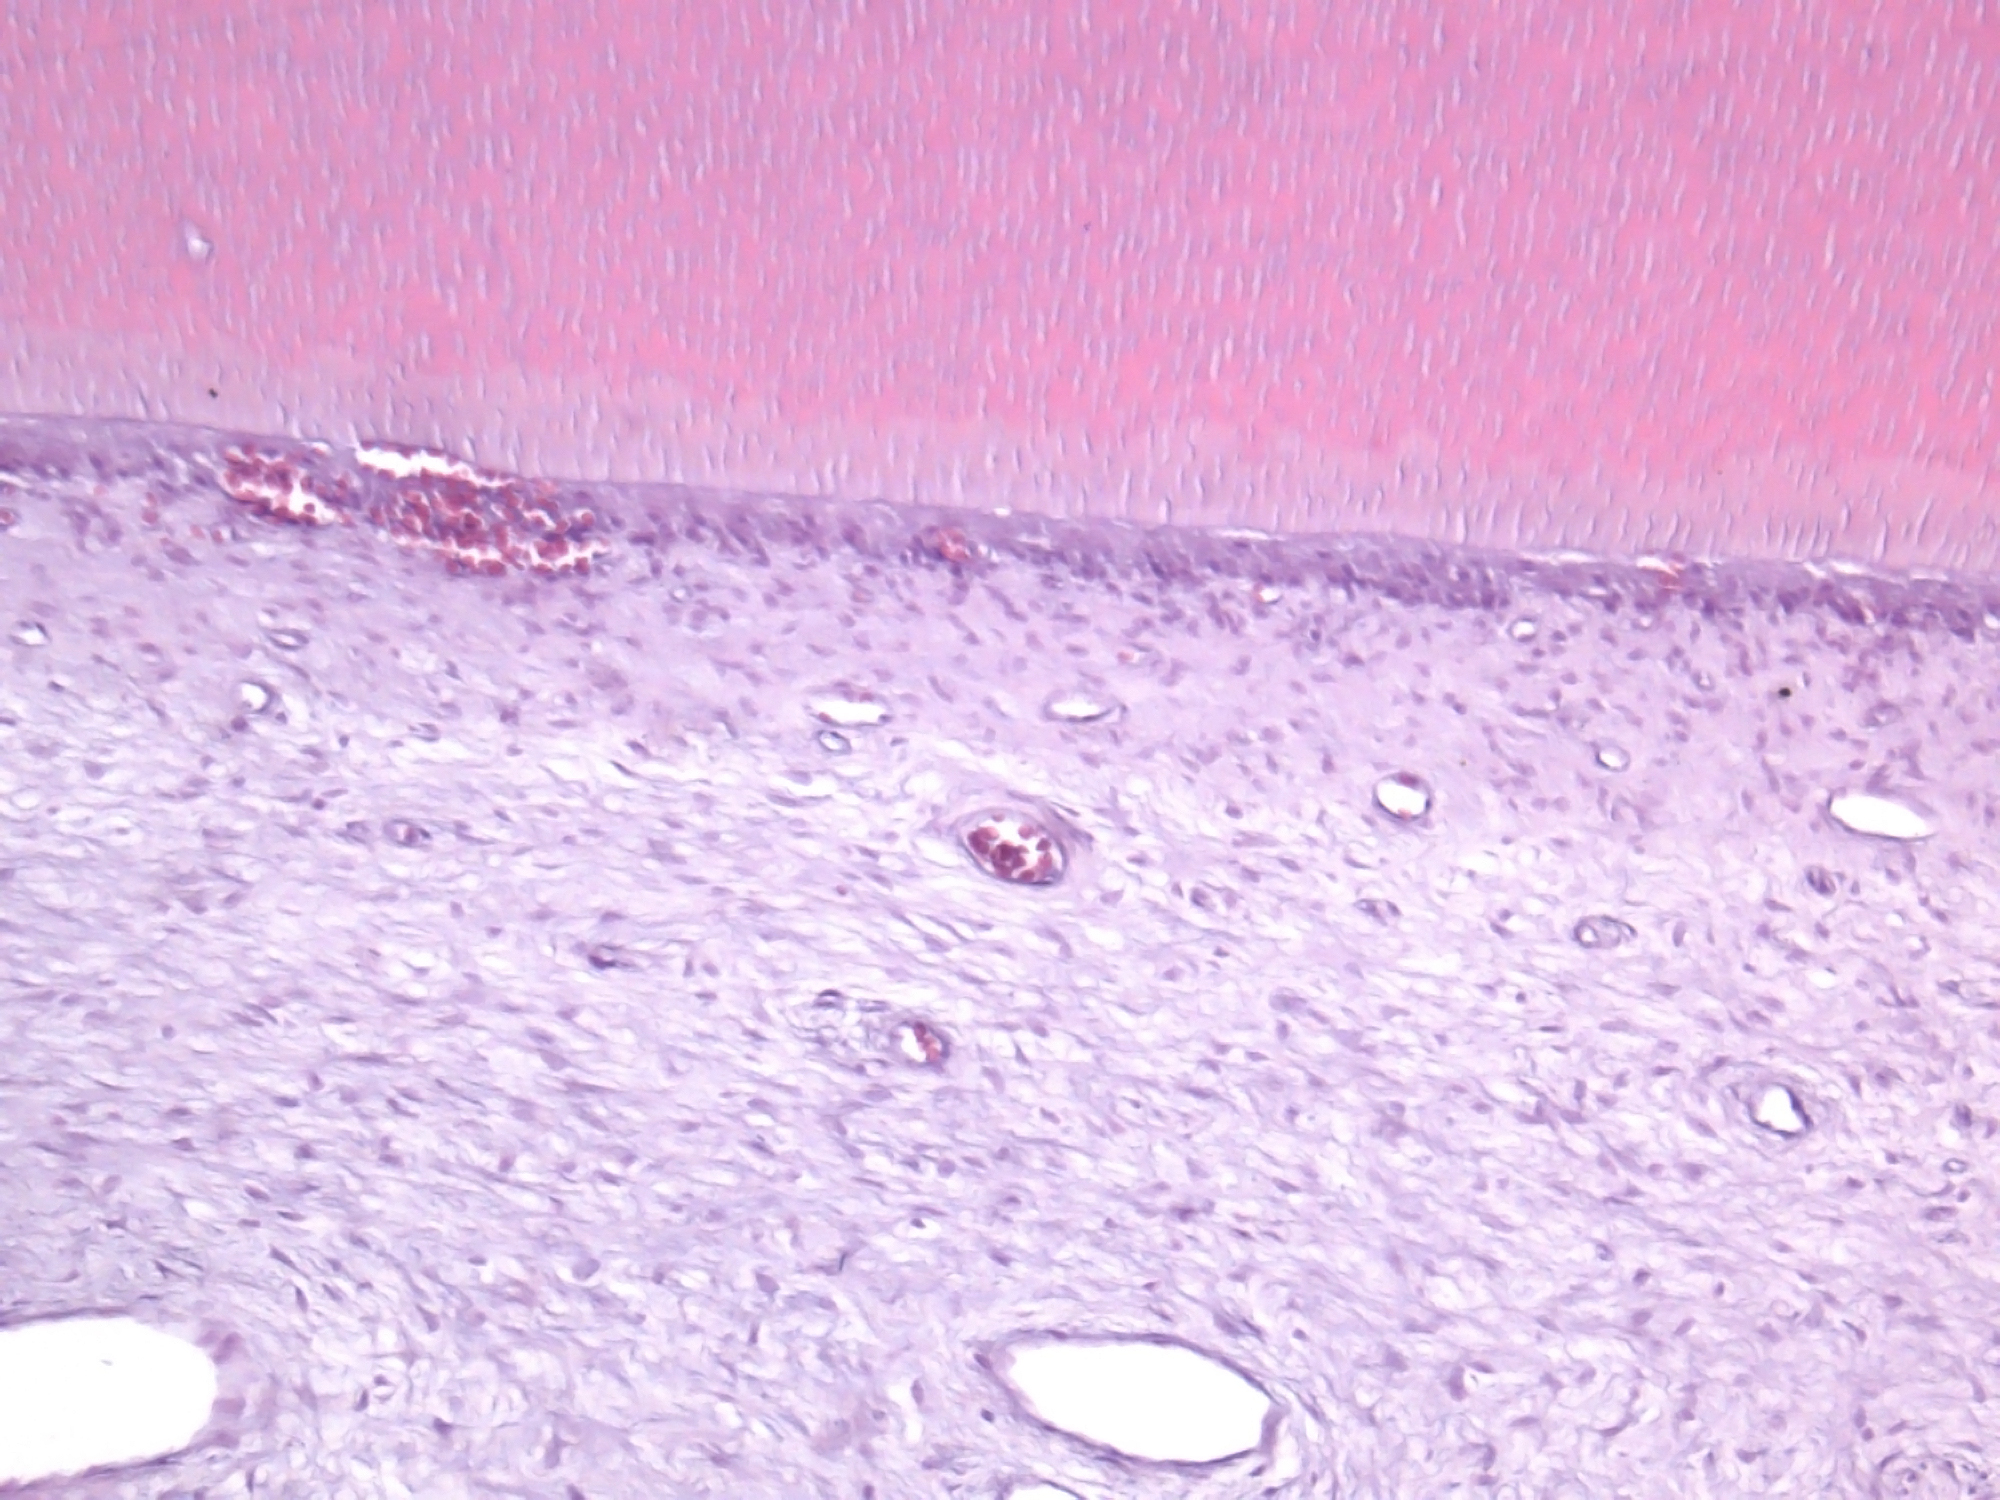

El laboratorio de histotecnología está especializado en el procesamiento histológico de muestras de tejidos blandos y/o de tejidos duros, mineralizados, permitiendo su análisis mediante microscopía óptica para fines de estudio, docencia e investigación. Se reciben muestras de consultorios externos y de servicios de nuestra institución para su diagnóstico anatomopatológico.

● Desparafinización y tinciones histológicas de rutina, como H/E, y tinciones especiales, como tricrómicos, PAS, AB, ATO y rojo alizarina.

● Decalcificación de tejidos mediante soluciones químicas o quelantes (como EDTA).

● Técnicas especiales como citología exfoliativa, transparentación de dientes, desgaste de tejidos duros.